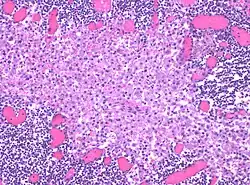

In medicine, histiocytosis is an excessive number of histiocytes[1] (tissue macrophages), and the term is also often used to refer to a group of rare diseases which share this sign as a characteristic. Occasionally and confusingly, the term histiocytosis is sometimes used to refer to individual diseases.

Histiocytosis is a rare disease, thus its diagnosis may be challenging. A variety of tests may be used, including:[5]